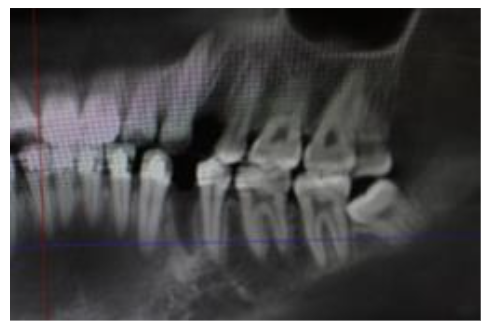

The bisected diagram shows the roots of the bicuspids, along with the adjacent roots of the second bicuspids and the canine, which nearly touch each other.

In cases of crowding, the canine is retracted to create space for aligning and correcting the inclination of the anterior teeth. The 2nd bicuspid will move mesially as a reciprocal force when the canine is retracted. The area in front of the 2nd bicuspid is the fresh wound of the extracted 1st bicuspid, and there was space. Alveolar bone density tends to decrease during orthodontic movement, as previously mentioned. Therefore, the primary retention in closing the extraction space in this situation is the distal movement of the canine; the density of these areas was measured and calculated. The density value was obtained using Planmeca Romexis software from the Planmeca Pro-Max x-ray machine. The space on the extraction side is the diameter of the root of the 1st bicuspid plus residual alveolar bone in the cervical area. The diameter of the cervix of the 1st bicuspid ranges from 4 to 5 mm at most. The result of accumulating and processing the data is the statistical mean and the standard deviation.